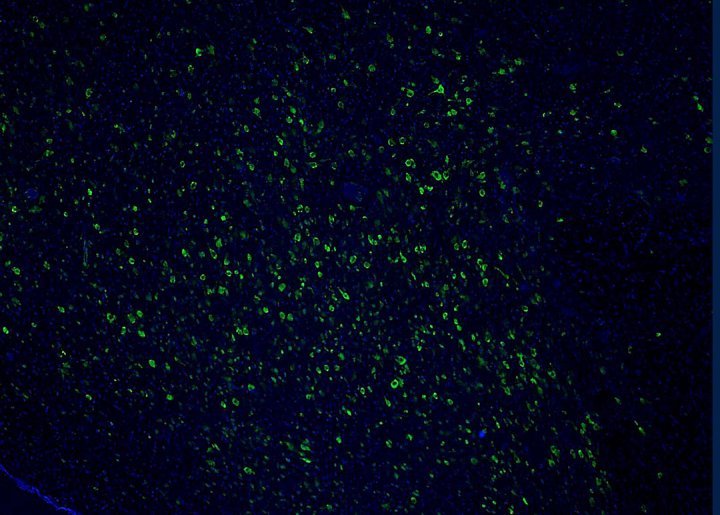

Per determinare ciò che contribuisce al degrado di questi neuroni nel MA, i ricercatori hanno esaminato il cervello di 33 pazienti con MA, 20 con PSP e 32 volontari che avevano avuto un cervello sano fino alla fine della vita. Il team ha misurato le quantità di due proteine spesso associate al processo neurodegenerativo: amiloide-beta (Aβ) e tau. Quale delle due è più coinvolta nella rottura del sonno è una domanda discussa da tempo; la maggior parte dei ricercatori addebita i problemi di sonno all'accumulo di Aβ.